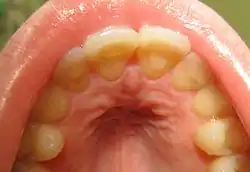

![]() فقدان مينا الأسنان من داخل الأسنان العلوية الأمامية كنتيجة للنهم العصبي فقدان مينا الأسنان من داخل الأسنان العلوية الأمامية كنتيجة للنهم العصبي | |

الاتصال المتكرر بين الأسنان والحمض المعدي، على وجه الخصوص، قد يسبب:

- تآكل الأضراس أو تآكل مينا الأسنان.[14]

الأشخاص المصابون بالنّهم العصبي هم أكثر عرضة للإصابة بالاضطرابات العاطفية كالاكتئاب واضطراب القلق العام من غيرهم. في عام 1985، قامت جامعة كولومبيا بعمل دراسة على إناث مصابات بالنهم في معهد ولاية نيويورك للصحة النفسية، ووجدت أن 70% منهنّ عانينَ من الاكتئاب في فترة ما من حياتهنْ (في حين أن النسبة لدى نساء العيّنة القياسية من عامّة الشعب كانت 25.8%)، وترتفع النسبة إلى 88% إذا أخذنا جميع الاضطرابات النفسية بعين الاعتبار.[22] وجدت دراسة أخرى أجرتها مستشفى الأطفال الملكي في ملبورن على جماعة من 2000 مراهقا أن من تنطبق عليه صفتان على الأقل من مقياس تشخيص النهام العصبي أو القهم العصبي الموجودة في الكتيب التشخيصي والإحصائي للأمراض العقلية تزداد احتمالية إصابتهم بالقلق 6 مرات وتتضاعف احتمالية إصابتهم بالإدمان على المخدرات.[23] بعض الذين يعانون من مرض فقدان الشّهية العصبي معرضون لنوبات من النهم العصبي من خلال قيامهم بالتطهير ( إما بالتقيؤ الذاتي أو تناول المسهلات) كطريقة سريعة لتخليصهم من الغذاء الموجود في أجسامهم.[24] للنهم العصبي آثار سلبية وخيمة على صحة أسنان المُصابين نتيجة مرور الأحماض المتكرّر خلال الفم أثناء التقيؤ مُسببًا تآكلًا حمضيًا خصوصًا على الأسطح الخلفية للأسنان.